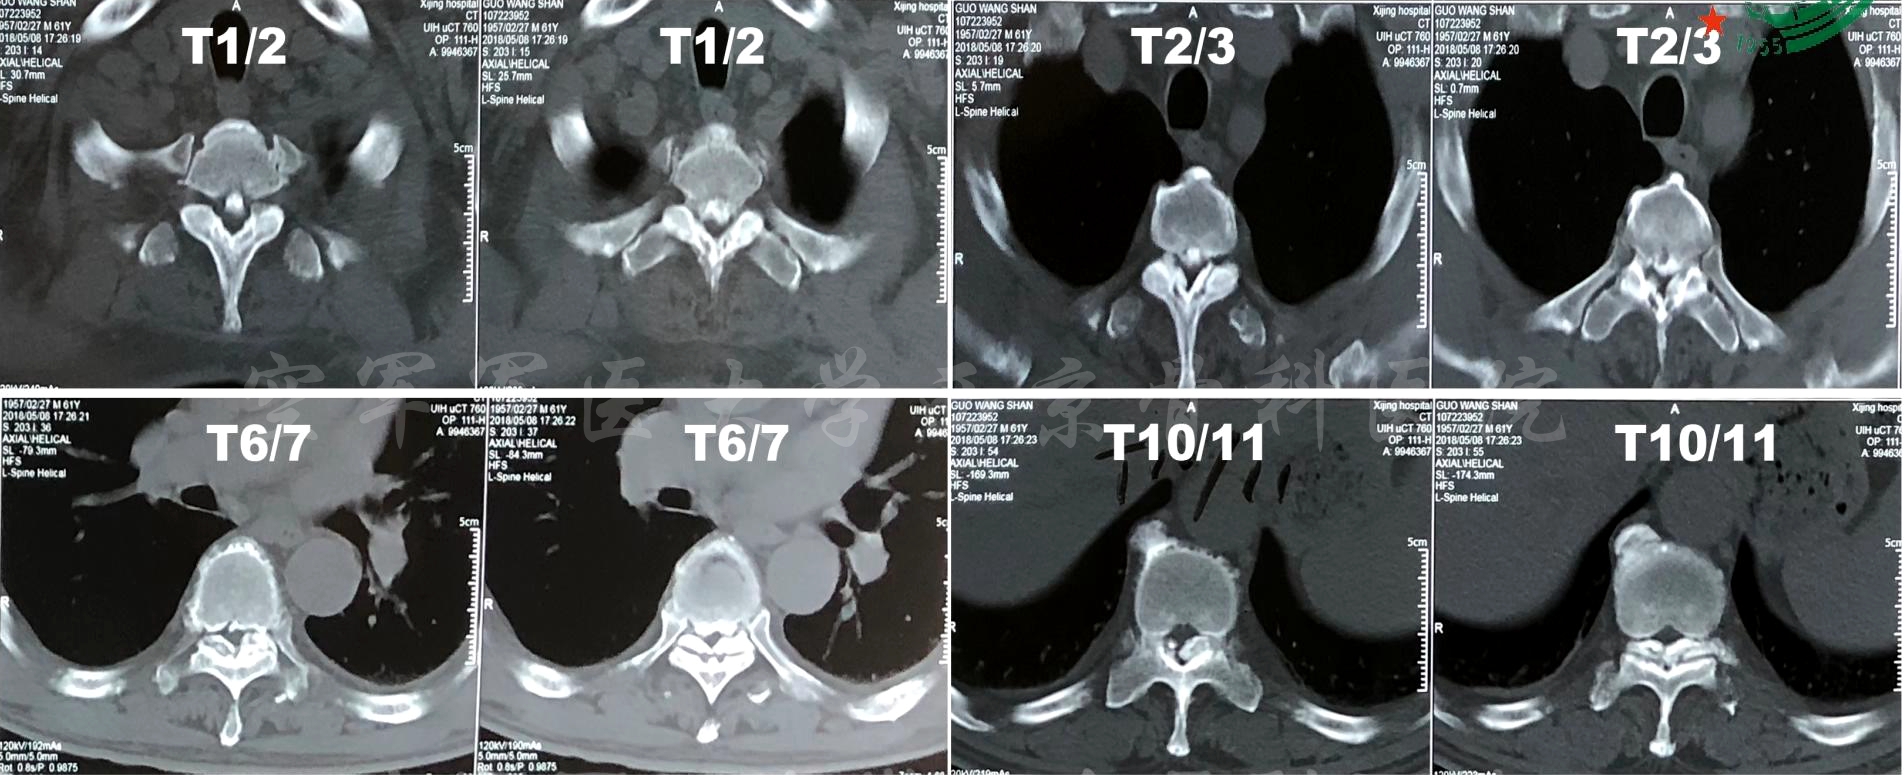

患者:女,75岁

主诉:双下肢麻木伴间歇性跛行1年半,加重8月。

双足底,左足背、拇指背侧及右拇指背侧皮肤感觉减退。腘绳肌左/右=Ⅳ/Ⅳ级,胫前肌左/右=Ⅳ/Ⅳ级,足拇背伸肌左/右=Ⅲ/Ⅳ级,趾伸肌左/右=Ⅲ/Ⅳ级,腓骨长短肌左/右=Ⅳ/Ⅳ级,小腿三头肌左/右=Ⅳ/Ⅳ级,趾屈肌左/右=Ⅳ/Ⅳ级,胫后肌左/右=Ⅲ/Ⅳ级,右侧跟腱反射消失,病理征阴性。

诊断:腰椎管狭窄症(L3-5)

术前X线正侧位片